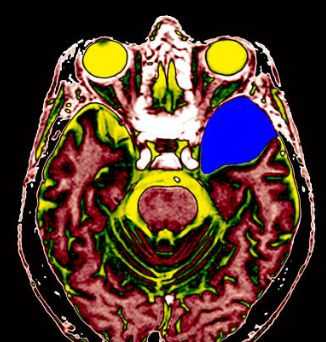

МРТ головного мозга. Т2-взвешенная аксиальная томограмма. Арахноидальная киста. Цветовая обработка изображения.

МРТ головного мозга. Арахноидальная киста полюса левой височной доли. Цветовая обработка.

Арахноидальные кисты представляют собой скопление ликвора между листками расщепленной паутинной оболочки. Арахноидальная киста обычно не сопровождается другими мальформациями. Незначительная часть арахноидальных кист имеет приобретенное происхождение - следствие лептоменингита, операции или кровоизлияния. Частота составляет около 1% от внутричерепных образований. Соотношение полов М:Ж, как 4:1. Типичная локализация - средняя черепная ямка (в области Сильвиевой борозды 50%), межполушарная щель, мосто-мозжечковый угол (11%), за скатом или на уровне четверохолмия (10%), в области червя мозжечка (9%), реже в области межножковой и предмостовой цистерн (3%), а также супраселлярной и хиазмальной цистерн. В зависимости от размера предложено делить кисты на 3 типа (Galassi, 2006), что однако, не имеет практического значения. Ретроцеребеллярная арахноидальная киста довольно часто встречаются за мозжечком и отличима от mega cisterna только по неизменённой задней черепной ямке. При МРТ головного мозга содержимое кисты чисто ликворное, стенки гладкие, чётко очерченные, внутри кисты могут быть перегородки. Мелкие арахноидальные кисты очень трудно увидеть при МРТ головного мозга. Меняя ширину окна и его уровень на Т1-зависимых МРТ изображениях можно заметить, что киста чуть светлее ликвора. Дифференциальная диагностика с эпидермальными кистами лучше осуществляется с помощью МРТ последовательности FLAIR. На них при МРТ головного мозга эпидермальные кисты становятся яркими, в отличие от гипоинтенсивных арахноидальных. Вероятно, вариантом арахноидальной кисты является нейроэпителиальная киста, которая при МРТ головного мозга имеет типичное расположение в области хориоидальной щели.

Арахноидальные кисты представляют собой скопление ликвора между листками расщепленной паутинной оболочки. Арахноидальная киста обычно не сопровождается другими мальформациями. Незначительная часть арахноидальных кист имеет приобретенное происхождение - следствие лептоменингита, операции или кровоизлияния. Частота составляет около 1% от внутричерепных образований. Соотношение полов М:Ж, как 4:1. Типичная локализация - средняя черепная ямка (в области Сильвиевой борозды 50%), межполушарная щель, мосто-мозжечковый угол (11%), за скатом или на уровне четверохолмия (10%), в области червя мозжечка (9%), реже в области межножковой и предмостовой цистерн (3%), а также супраселлярной и хиазмальной цистерн. Ретроцеребеллярная арахноидальная киста довольно часто встречаются за мозжечком и отличима от mega cisterna только по неизменённой задней черепной ямке. Содержимое кисты чисто ликворное, стенки гладкие, чётко очерченные, внутри кисты могут быть перегородки. Мелкие арахноидальные кисты очень трудно увидеть. Меняя ширину окна и его уровень на Т1-взвешенных МРТ изображениях можно заметить, что киста чуть светлее ликвора. Дифференциальная диагностика с эпидермальными кистами лучше осуществляется с помощью МРТ последовательности FLAIR. Эпидермальные кисты становятся яркими, в отличие от гипоинтенсивных арахноидальных.